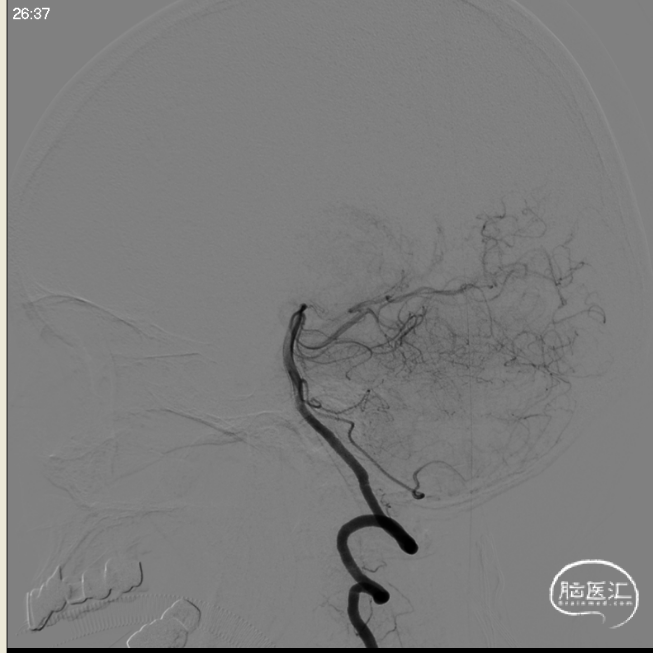

术后即刻影像及患者术后情况

标准正位

标准侧位

支架CT

术后CT

建立通路是颅内血管病介入治疗最基础环节。良好的中间导管应具备到位顺畅、支撑稳定等优点。SKATHI远端通路导管作为一款优秀的国产中间导管,在此病例中,可以轻易的裸奔通过极度迂曲的颈内动脉,顺利到达目标段,表现出了极强的过弯能力,并可以为微导管提供稳定的支撑,在后续的输送辅助支架及弹簧圈过程中,系统很稳定,提高了手术效率和安全性。